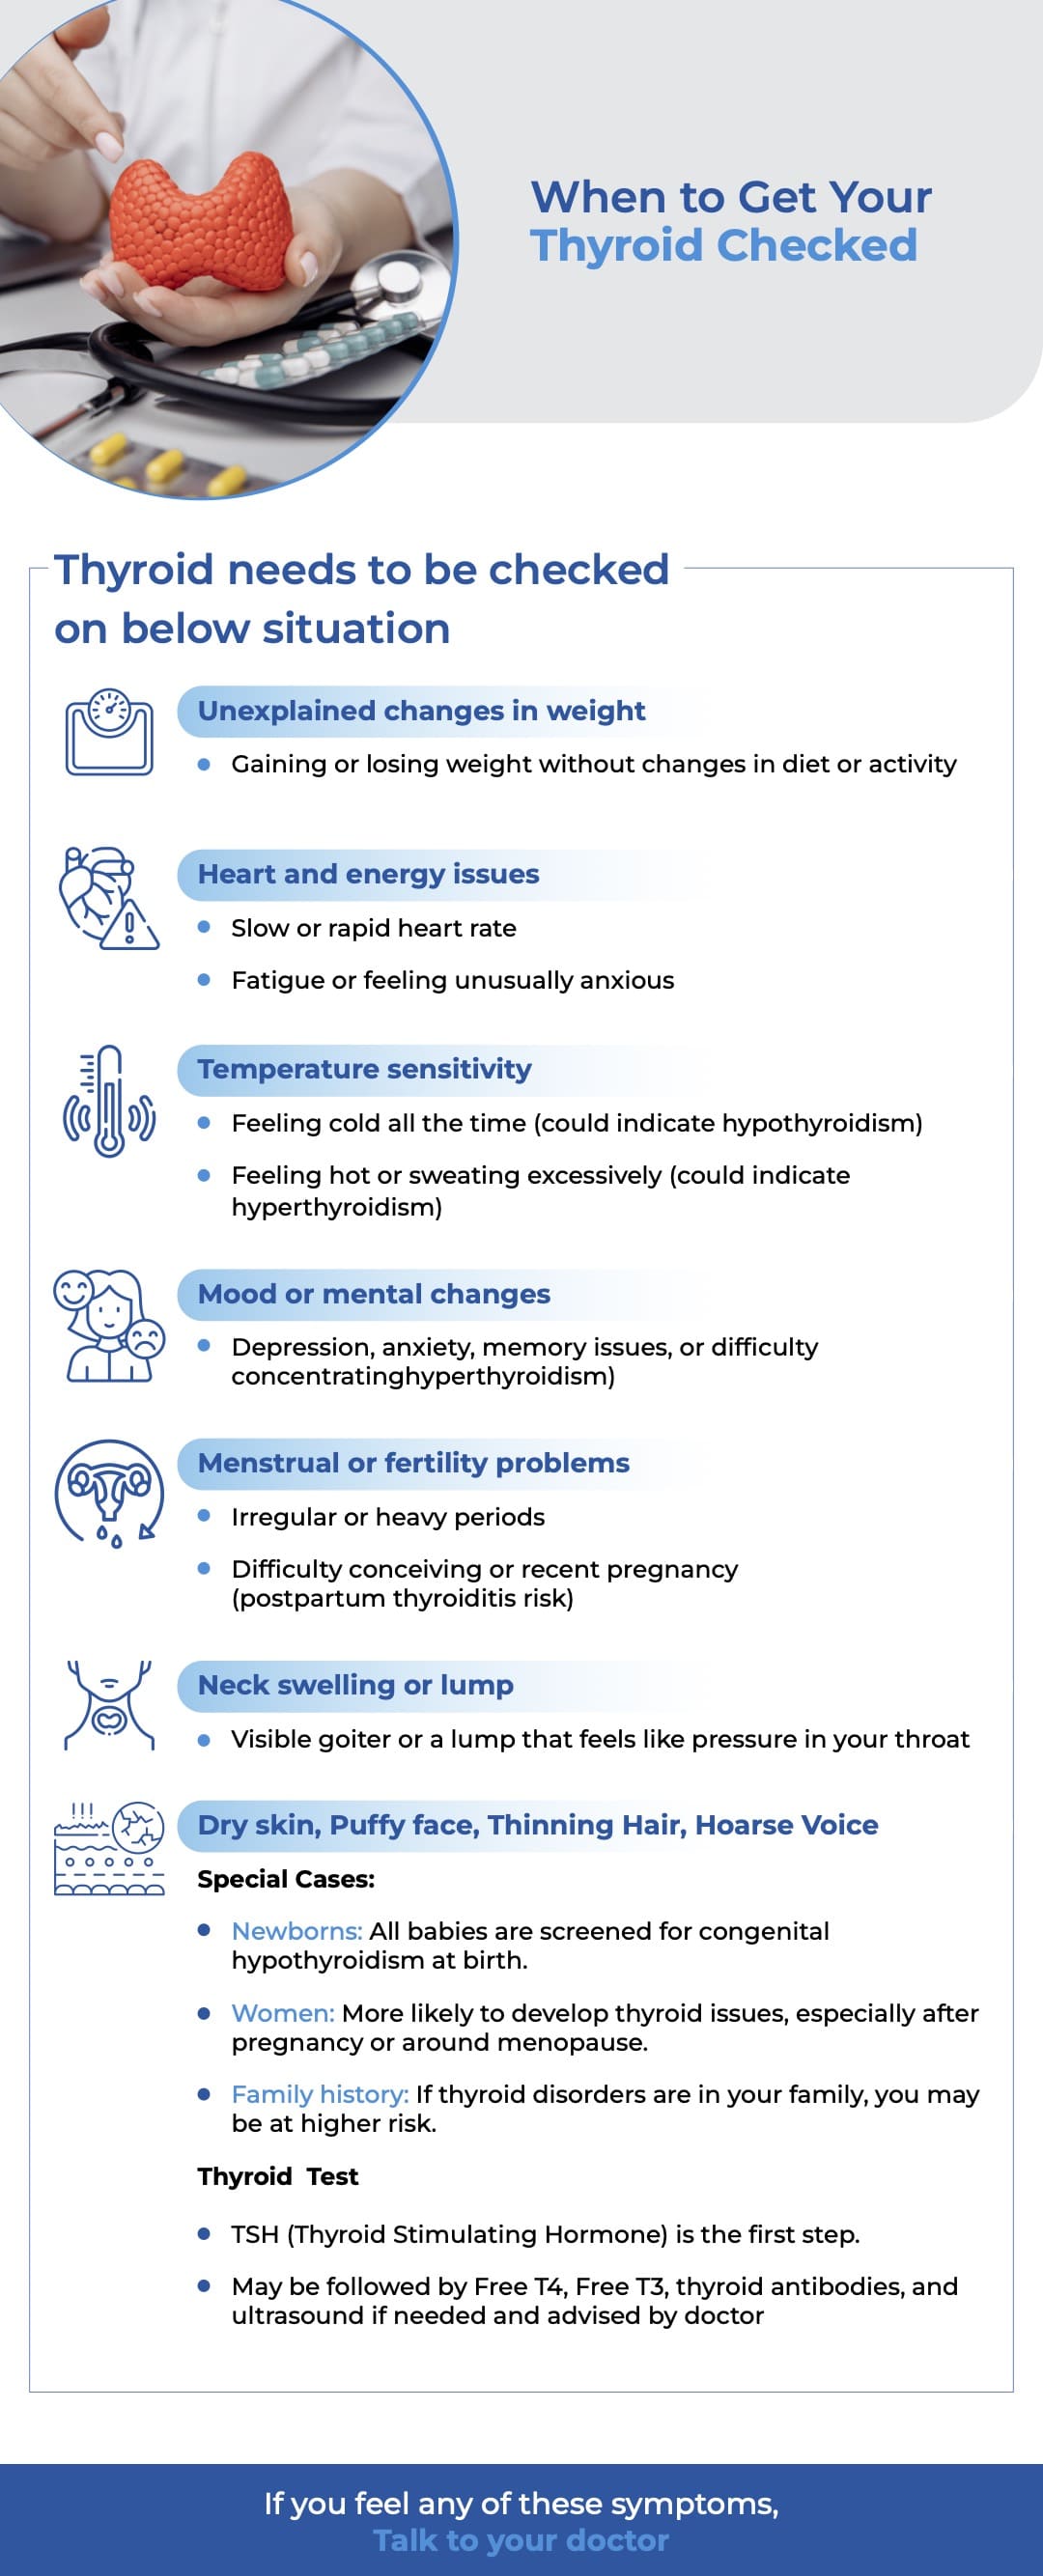

Thyroid Disease

When to Get Your Thyroid Checked